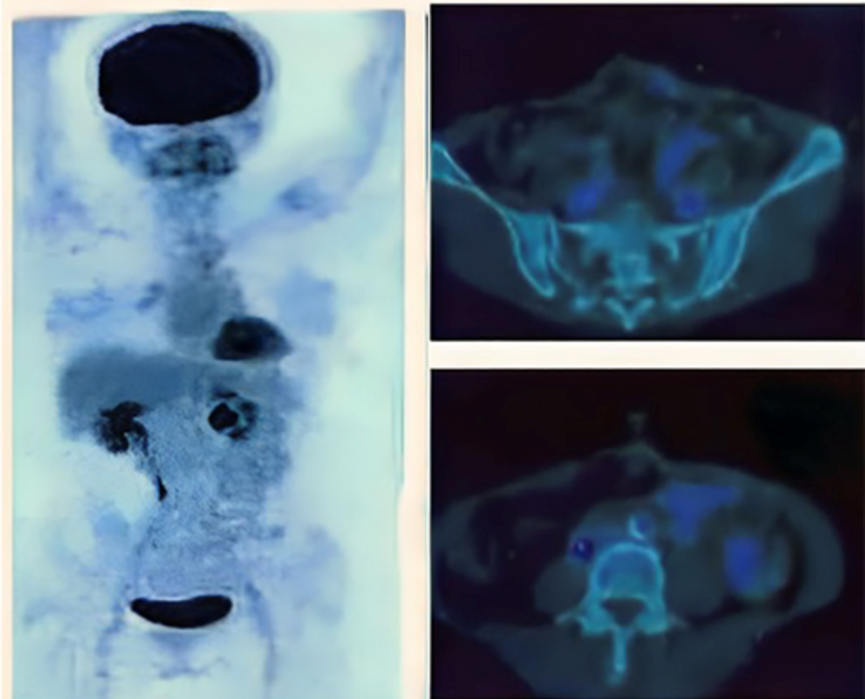

在国内,也有科研人员将NK细胞应用到结直肠癌患者的相关治疗研究研究中。研究人员采用靶向NKG2D的CAR-NK细胞疗法治疗结直肠癌患者后,NK细胞疗法可以缓解患者如腹水等并发症,延缓患者肿瘤发展趋势[2]。

该研究中接受NK细胞治疗的是3 例转移性结直肠癌患者。当前两名患者接受了低剂量的CAR-NK细胞腹腔内输注后,实验数据观察到腹水生成量明显减慢以及腹水样本中肿瘤细胞的数量急剧减少。第三例肝转移癌症患者采用超声引导下瘤内经皮注射和腹腔内灌注方式输注 CAR-NK细胞后,经多普勒超声检查,观察到肝部肿瘤也快速缩小。

图源文献【2】NK 细胞治疗后, PEC-CT 结果显示患者病情明显缓解